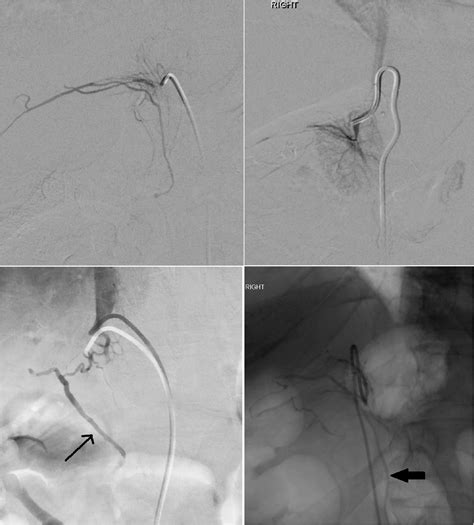

Adrenal Vein Sampling is performed by an interventional radiologist. The patient is usually awake or under mild sedation, as the procedure requires the patient to remain still while catheters are navigated through the venous system. Because the adrenal veins are small and anatomically challenging, the procedure requires high technical skill.

• Selective Cannulation: The radiologist navigates the catheter into the right and left adrenal veins to collect precise blood samples.

• Hormone Measurement: Blood is drawn from both adrenal veins and a peripheral vein for comparison. Cortisol levels are measured alongside aldosterone to confirm the catheter is correctly positioned in the adrenal vein rather than a nearby renal vein.

⚠️ Note: Successful cannulation of the right adrenal vein is notoriously difficult due to its small size and direct entry into the inferior vena cava. Patients should ensure their procedure is performed at an experienced tertiary center with a high volume of cases to reduce the risk of technical failure.